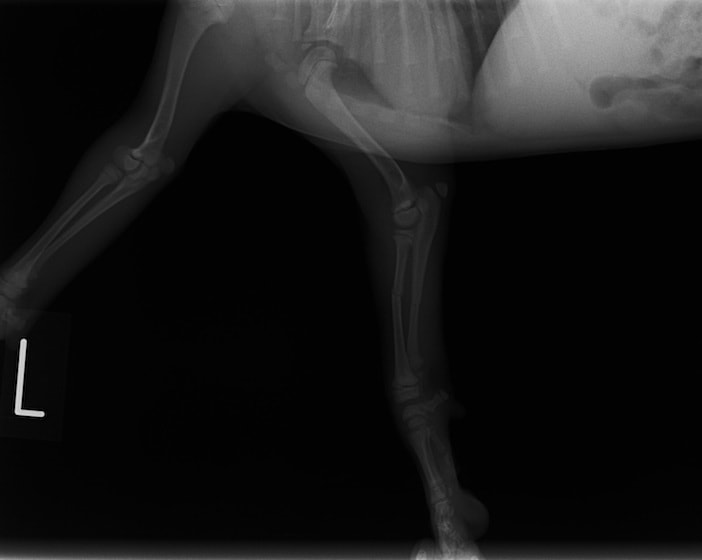

ペルシャ猫 11ヶ月齢 雄

他院にて左大腿骨遠位の成長板骨折(salter-harrisⅠ型)が認められており、治療相談を目的として来院。当院にて、キルシュナーワイヤーを用いたピンニングにより骨折部位の整復を行いました。術後の経過は良好で、現在も経過観察中です。

術前レントゲン